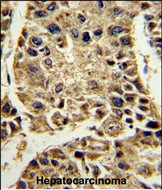

- Formalin-fixed and paraffin-embedded human hepatocarcinoma reacted with SERPINA4 Antibody (C-term), which was peroxidase-conjugated to the secondary antibody, followed by DAB staining. This data demonstrates the use of this antibody for immunohistochemistry; clinical relevance has not been evaluated.